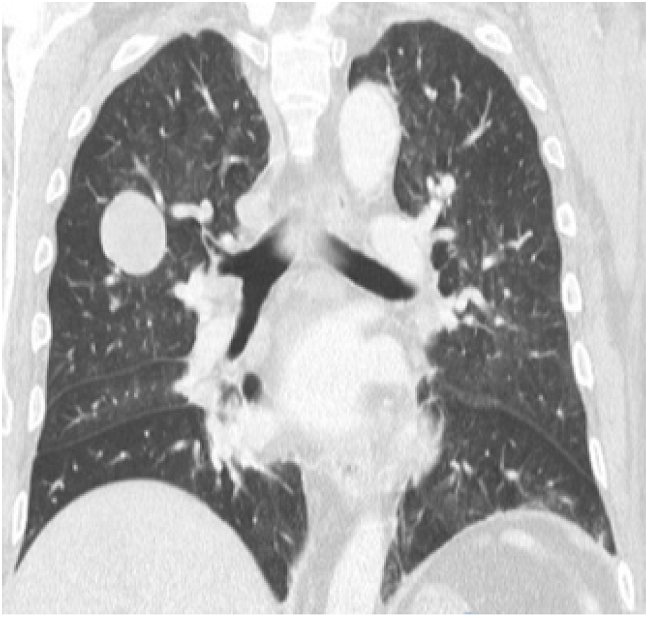

Initially, management was given to compensate for heart failure. Considering his medical history and the presence of a mass in the upper right lobe, a computed tomography (CT) of the thorax was performed in which a mass in the upper right lobe of 38x29x29mm was observed, without enhancement after the administration of contrast medium. It also showed three other nodular images with the same characteristics in the apical segment of the upper left lobe with a secondary neoplastic aspect (Figure 1).